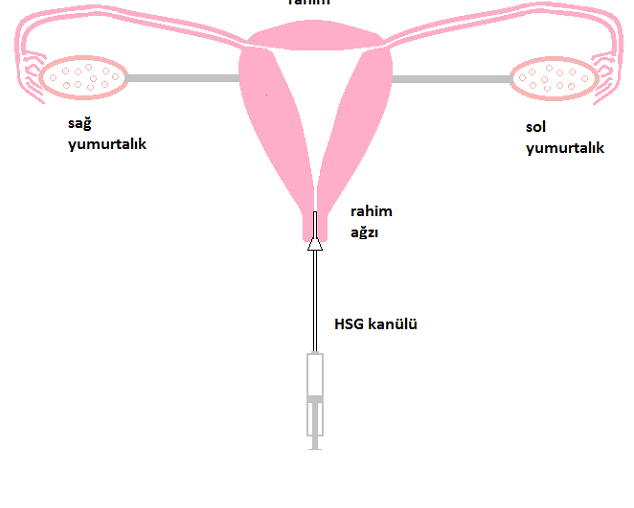

في عيادتنا ، يتم إجراء HSG في معظم الحالات دون ألم وفي بعض الحالات مع القليل من الانزعاج (الانزعاج مثل آلام الدورة الشهرية). يوضع الجهاز في عنق الرحم ويتم إعطاء الدواء الملون وتصويره.

يظهر الشكل التشريحي الطبيعي للرحم والأنابيب في الشكل.

يوضح الشكل البنية التشريحية الطبيعية للرحم وقناتي فالوب.